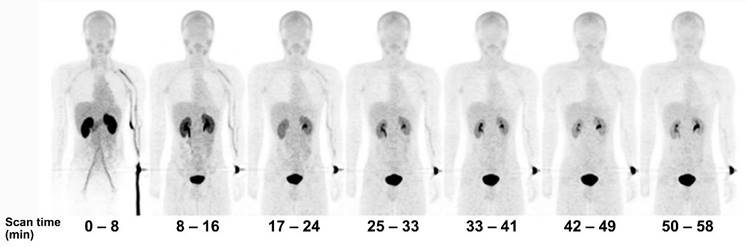

Figure 2

Serial PET mean intensity projection (MIP) images of [18F]FBPA uptake in a healthy male. Kidney and pancreas uptake [18F]FBPA rapidly cleared after injection. Pelvic kidney and bladder accumulation represent [18F]FBPA excretion route. A high-contrast image can be obtained less than 1 hour after injection [65]. Adapted and reproduced with permission from Springer Nature. Copyright © 2016, The Japanese Society of Nuclear Medicine.

[18F]FBPA is claimed as LAT1-specific (Km LAT1 = 197 µM, Km ratio LAT2/LAT1=14), while BPA has much lower LAT1-specificity (Km ratio LAT2/LAT1 = 4.3) [62]. In melanoma, [18F]FBPA is involved in melanogenesis, and thus melanoma lesions have higher [18F]FBPA uptake [57]. Adding the α-methyl group might improve the LAT1 selectivity (this tracer is still in early investigation) [63]. As a LAT1 substrate (subject to bi-directional transport), consequently, [18F]FBPA tumor uptake is generally lower than PET radiotracers whose trapping mechanism within cancer cells, like [18F]FDG. However, [18F]FBPA tumor uptake is about similar to that of [11C]MET [64]. A high-contrast image in [18F]FBPA PET can be obtained earlier than the typical 60 min post-injection scan (Figure 2) [65]. [18F]FBPA PET visualized thoracal and mediastinal malignant lesions with high contrast (Figure 3A) [66]. In benign lesions, [18F]FBPA uptake was consistently low (SUVmax < 2), while [18F]FDG uptake on the same lesions was higher (SUVmax > 5). More importantly, unlike [11C]MET and [18F]FDG, [18F]FBPA does not accumulate in inflammatory tissues, including post-radiation necrotic lesions (Figure 3B) [67].